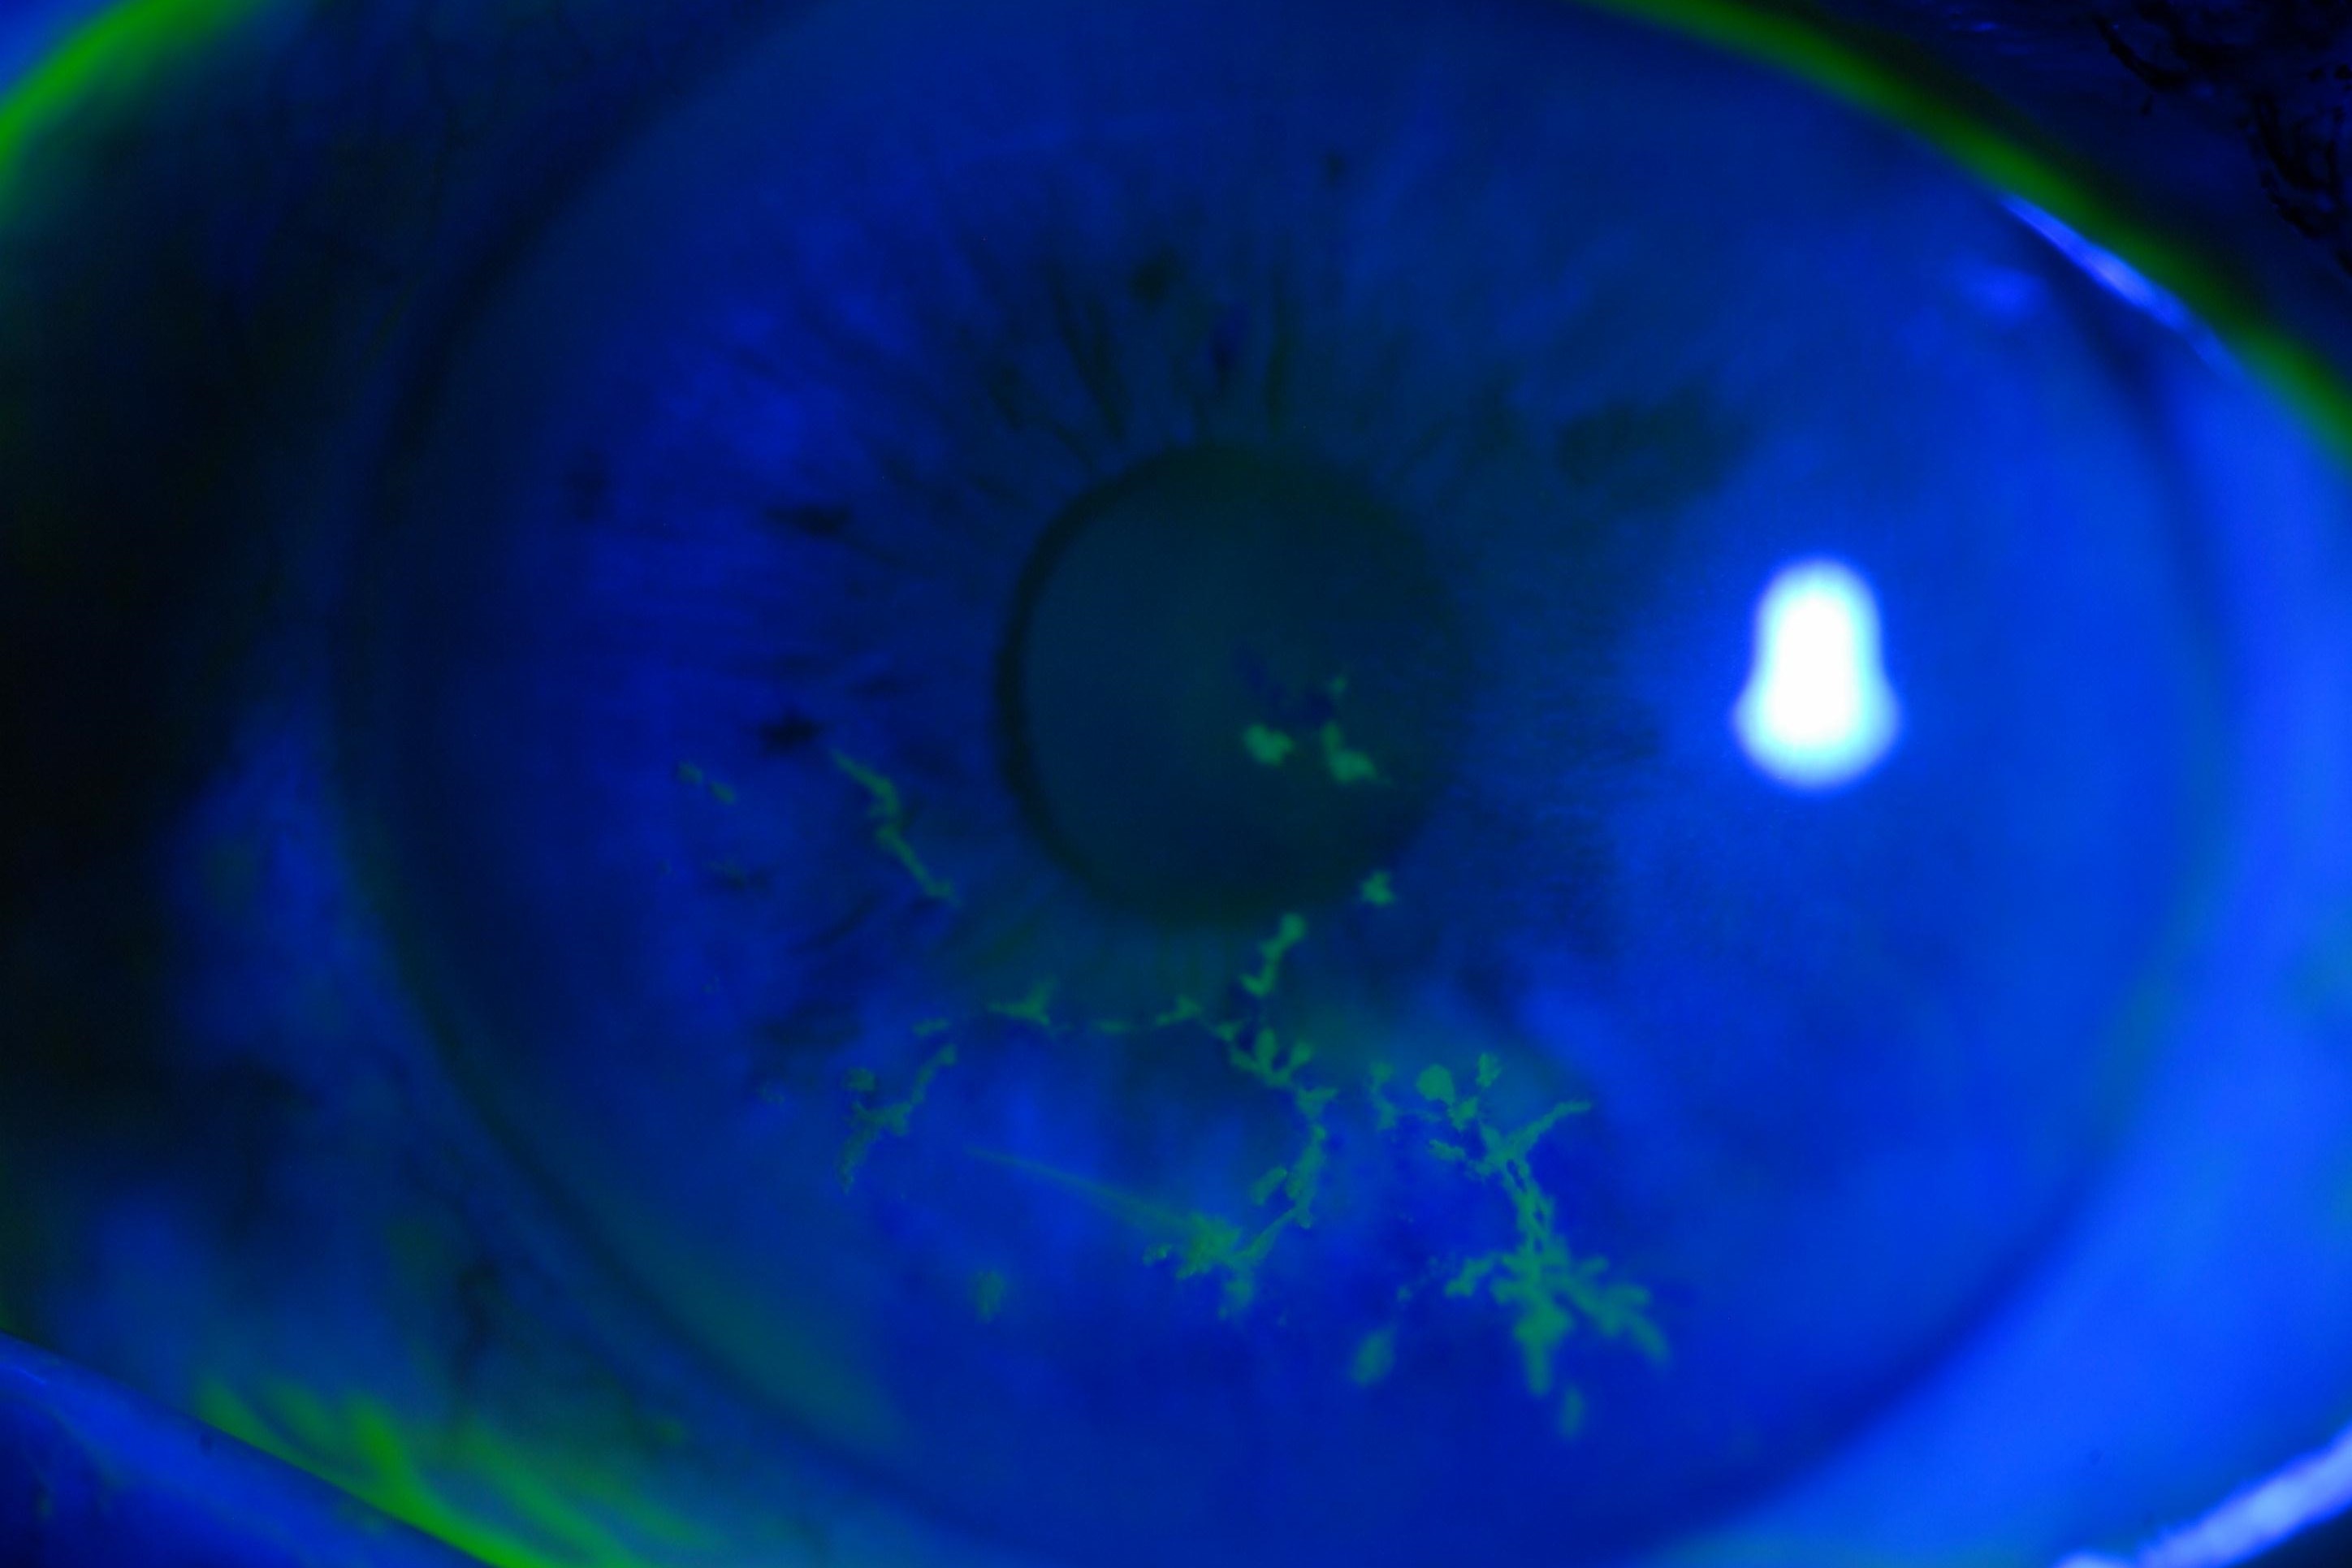

Herpes zoster virus keratitis

Herpes Zoster Ophthalmicus (HZO) is the reactivation of varicella zoster virus infection in the ophthalmic branch of the trigeminal nerve. Ocular complications of HZO include keratitis, uveitis, trabeculitis and, less commonly, optic neuritis and cranial nerve palsy. HZO can lead to chronic and recurrent ocular inflammation and secondary glaucoma.

Cataract formation is common in eyes with HZO due to the combined effect of age, ocular inflammation and corticosteroid use. Cataract surgery in these patients can be complicated by the presence of corneal scarring, previous uveitis and recurrence of disease after surgery. However, little is known of the outcomes of cataract surgery in this group. Therefore, we carried out a retrospective review of patients undergoing cataract surgery after HZO, to evaluate the complications, visual outcomes and recurrence rates.